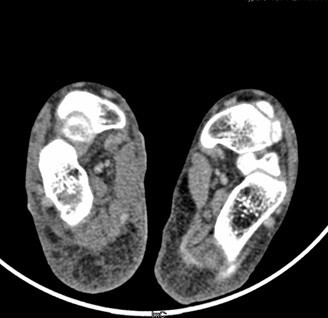

患者男,15岁,因“车祸致右足跟部皮肤撕脱伤清创缝合术后13天”入院。患者13天前因车祸导致右足疼痛流血伴功能障碍,右足跟部皮肤撕脱,遂到当地人民医院就诊,诊断为右跟骨骨折伴跟部皮肤严重剥脱伤,右胫骨远端骨折。急诊下行“右足跟部皮肤严重剥脱伤皮肤严重挫裂伤清创缝合术”。术后给予止痛、消肿、预防感染等对症处理,目前右足外侧及跟部皮肤变暗,坏死。患者为进一步诊疗,故转入我科继续治疗。

查体:右足内踝、外踝及跟部皮肤变暗,部分缺血坏死。未见畸形,稍肿胀。右足趾皮温无明显降低,右足趾感觉未见明显异常。右足内踝、外踝及跟部皮肤局部压痛。右踝关节活动受限,右踝关节活动诱发疼痛。右膝关节活动未见明显异常。 辅查:x片示右跟骨,右胫骨远端骨折。

诊断:1、右足清创缝合术后皮肤软组织坏死伴感染,2、右跟骨骨折,3、右胫骨远端骨折。 治疗:择期手术。